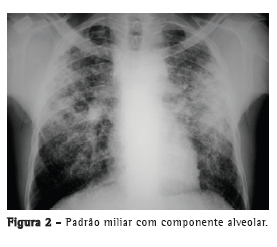

Com relação aos achados radiológicos, infiltrados reticulares e consolidação são os padrões mais frequentes,(5,6,10,15,17) sendo que cavitação pode estar presente em 27-50% dos casos.(6,10,16) As Figuras 1 a 4 mostram alguns dos principais padrões radiológicos nesse contexto.

O tempo entre o início dos sintomas e o início do tratamento antituberculose descrito nos estudos foi maior do que 30 dias em 28,8-34,0% dos casos.(6,17) O tempo entre a admissão e o início da terapêutica adequada foi avaliado em apenas um estudo, sendo relatada uma média de 4,3 dias. Naquele estudo retrospectivo, o tempo entre a admissão e o início do tratamento foi menor nos pacientes com tuberculose miliar do que naqueles com pneumonia tuberculosa (2,8 ± 2,5 dias vs. 5,0 ± 7,0 dias; p = 0,048).(16) Pode haver atraso no diagnóstico e, consequentemente, no começo do tratamento pela difícil diferenciação radiológica entre pneumonia tuberculosa e pneumonia bacteriana grave. Considerando essa dificuldade na distinção entre as duas patologias, um estudo avaliou as diferenças nas características clínicas e radiológicas de pacientes com pneumonia grave com e sem tuberculose internados em UTIs. A história de sintomas com duração maior do que duas semanas e a presença de micronódulos ou de padrão cavitário na radiografia de tórax foram significativamente associados com tuberculose pulmonar ativa.(20) Adicionalmente, o padrão miliar na radiografia de tórax também pode ser erroneamente interpretado como insuficiência cardíaca congestiva.(18)